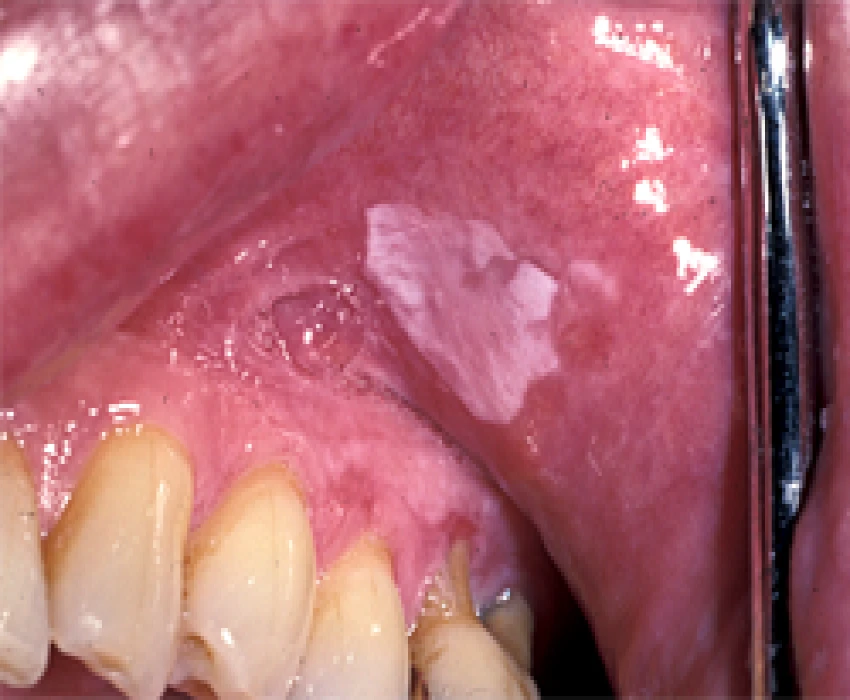

The red and white lesions include different type of lesions and to understand the various colors of these lesion one has to know, the color of oral mucous which depends on the degree of keratinization, dilation, and concentration of blood vessels, the amount of melanin pigment present in the epithelium and thickness of the epithelium. The professional require a skillful knowledge to diagnose and distinguish between these lesions and clinical correlation plays a very important role in diagnosing apart from histological reports. Dr Ankur has a deep insight in the above area.